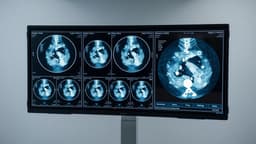

Bowel cancer remains a significant health concern in the UK, ranking as the fourth most common cancer and the second leading cause of cancer deaths. While screening has helped in older populations, a notable increase in diagnoses among younger individuals is occurring, with projections indicating a doubling of cases between 2010 and 2030. This trend has prompted researchers at The Institute of Cancer Research (ICR) in London to initiate a groundbreaking study.

The "Boomers Project" involves a meticulous comparison of bowel cancer specimens dating back to the 1950s, preserved at St Marks Hospital, with contemporary cancer samples. The core hypothesis is that changes in the "exposome"—encompassing shifts in diet, lifestyle, and environmental exposures over the decades—are contributing to the alarming rise in early-onset bowel cancer. Scientists are investigating various theories, including dietary habits, microplastic exposure, and microbiome alterations.

This comparative genomic analysis aims to illuminate how environmental influences have shaped cancer DNA over time. If successful, the study could offer crucial insights into the causes of bowel cancer in young people, potentially leading to new prevention and treatment strategies. Experts emphasize the importance of a healthy lifestyle and prompt medical consultation for any new bowel symptoms in reducing risk.